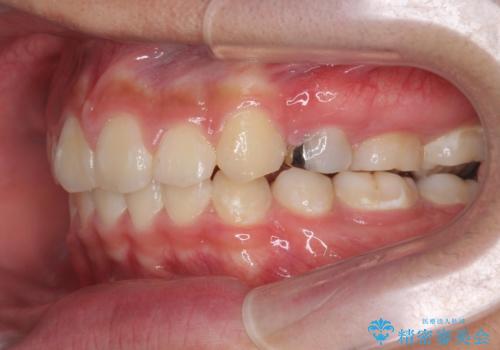

- 前歯のがたつきが原因で歯ブラシしづらい、見た目を改善したい!と矯正治療を希望され来院されました。

スペースの不足が見られるため、小臼歯の4本抜歯を行いマルチブラケットを用いた矯正治療を計画します。

噛み締めが強く、治療に時間がかかりましたが矯正治療の仕上がりに満足いただくことができました。